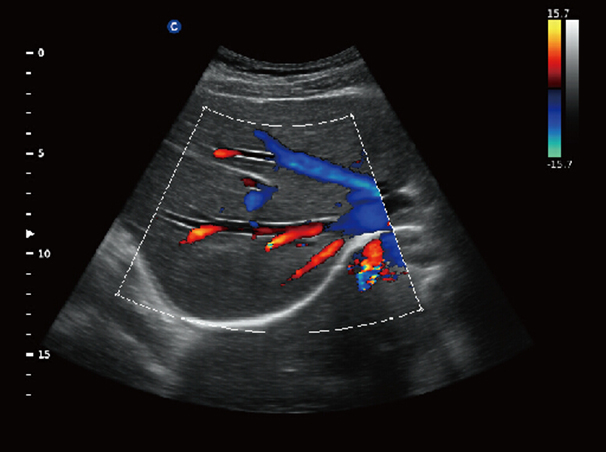

Chison Qbit 3 Color Doppler Digital Ultrasound Machine

Chison Qbit 3 A Slim Console Color Doppler System, Offers Ideal Patient Care With Its Easy Mobility, Smart Features, Significant Performance And Streamlined Workflow, To Strengthen The Clinical Confidence And Speed The Diagnostic Decision.

Chison QBit-3 Ultrasound Machine System, Offers Ideal Patient Care With Its Easy Mobility, Smart Features, Significant Performance And Streamlined Workflow, To Strengthen The Clinical Confidence And Speed The Diagnostic Decision.